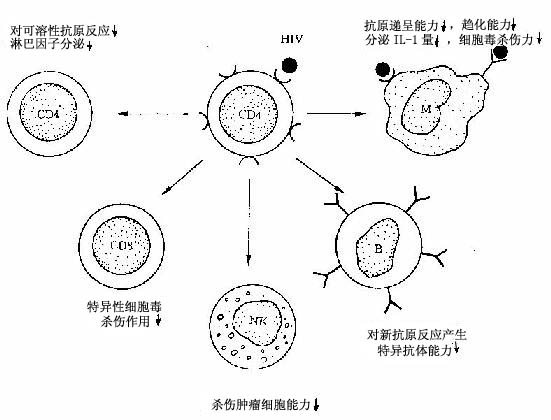

HIV选择性地侵犯和破坏TH细胞是AIDS发病的症结所在,由于HIV与TH细胞表面的CD4分子高度亲和,因而CD4分子可认为是HIV的受体乃入侵门户。HIV为一种C型逆转录病毒,分核心及包壳二大部分,包壳的糖蛋白gp120和ap41可先后与TH细胞膜上的CD4分子结合而进入TH细胞。在细胞内,病毒基因经逆转录而产生前病毒DNA,后者一经整合到宿主细胞的DNA,即可转录出完整的病毒颗粒,大量病毒颗粒在CD4+细胞膜处通过出芽而释放,并导致该细胞的溶解和死亡。由于TH细胞是调节整个免疫系统的枢纽细胞,TH细胞的消减必然影响到IL-2、γ-干扰素以及激活巨噬细胞、B细胞等有关的多种淋巴因子的分泌,将进一步影响TH细胞及其他免疫活性细胞的功能,包括:①TH细胞克隆增生和混合淋巴细胞反应降低,淋巴因子减少,对可溶性抗原的反应也减弱;②Ts(Tc)细胞克隆增生降低,特异性细胞毒反应减少;③NK细胞杀灭肿瘤细胞的功能降低;④B细胞在特异性抗原刺激下不产生正常的抗体反应,而原因不明的激活和分化引起高丙种球蛋白血症;⑤巨噬细胞对一般信号无反应,溶解肿瘤细胞、杀灭胞内寄生菌、真菌、原虫的功能减弱(图4-14)。

图4-14 HIV侵犯TH细胞后免疫调节障碍示意图